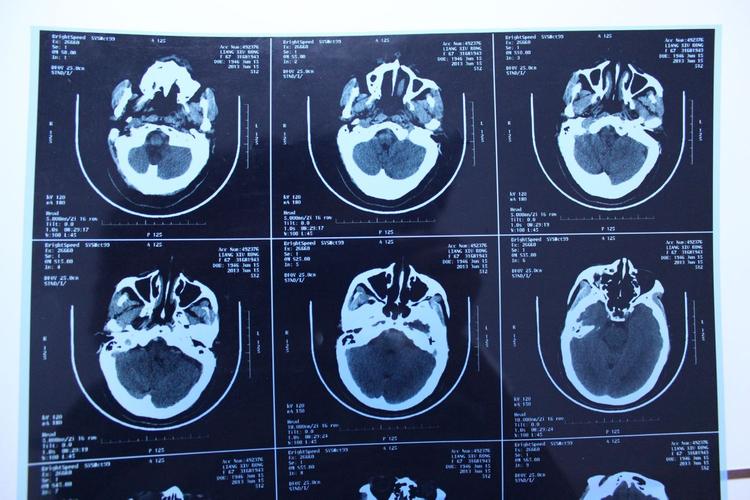

CT(计算机断层扫描):

- 急性期脑梗塞(几个小时到几天内): 早期可能看不出异常,24小时后才会显示为低密度(发黑)的区域。

- 慢性期脑软化灶: 表现为边界清晰的低密度(发黑)区域,形态不规则,像一个“洞”。